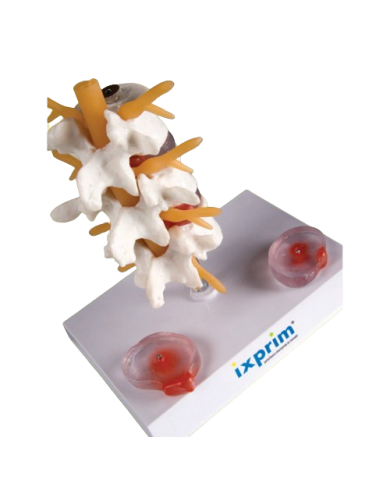

Modello anatomico PER FORNITURE CASE FARMACEUTICHE

Modello anatomico PER FORNITURE CASE FARMACEUTICHE

Modello anatomico PER FORNITURE CASE FARMACEUTICHE

Modello anatomico PER FORNITURE CASE FARMACEUTICHE

Modello anatomico PER FORNITURE CASE FARMACEUTICHE

Modello anatomico PER FORNITURE CASE FARMACEUTICHE

Modello anatomico PER FORNITURE CASE FARMACEUTICHE

Modello anatomico PER FORNITURE CASE FARMACEUTICHE

Modello anatomico PER FORNITURE CASE FARMACEUTICHE

Modello anatomico PER FORNITURE CASE FARMACEUTICHE

Modello anatomico PER FORNITURE CASE FARMACEUTICHE

Modello anatomico PER FORNITURE CASE FARMACEUTICHE

Modello anatomico PER FORNITURE CASE FARMACEUTICHE

Modello anatomico PER FORNITURE CASE FARMACEUTICHE

Modello anatomico PER FORNITURE CASE FARMACEUTICHE

Modello anatomico PER FORNITURE CASE FARMACEUTICHE

Modello anatomico PER FORNITURE CASE FARMACEUTICHE

Modello anatomico PER FORNITURE CASE FARMACEUTICHE

Modello anatomico PER FORNITURE CASE FARMACEUTICHE

Modello anatomico PER FORNITURE CASE FARMACEUTICHE

Modello anatomico PER FORNITURE CASE FARMACEUTICHE

Modello anatomico PER FORNITURE CASE FARMACEUTICHE